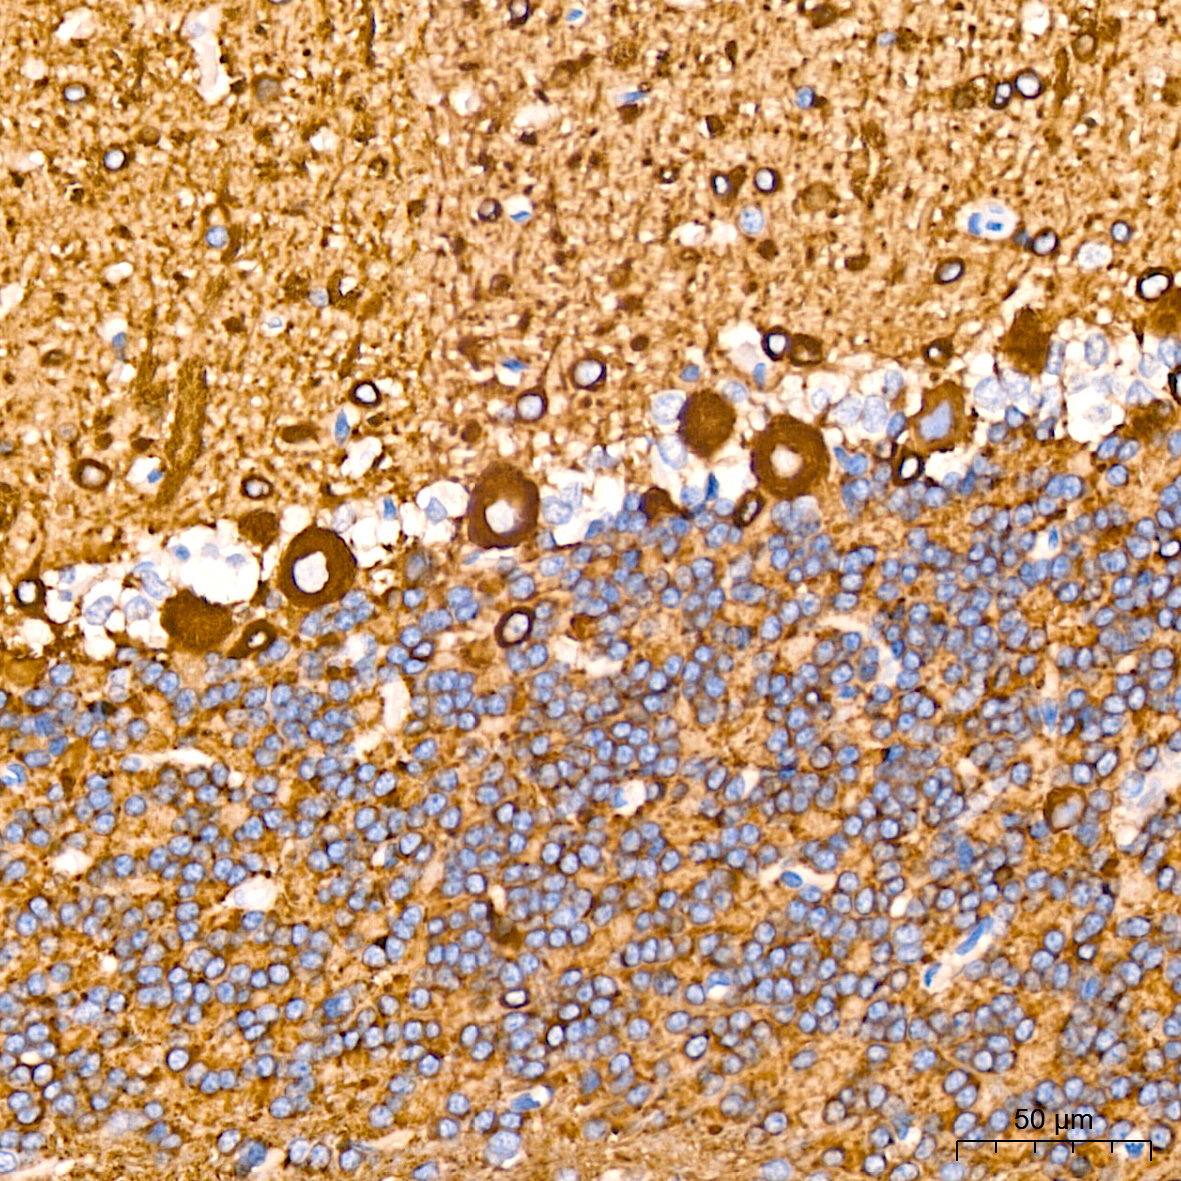

研究大脑和神经系统不仅需要检查神经元,而且还需要检查神经上皮细胞,胶质细胞。显示和识别这些各种细胞类型的关键在于使用靶向这些细胞内特异性表达并位于这些细胞内的蛋白生物标记物的抗体。下面列出了研究中最常见的一些标志物:

| 神经元 | βIII-Tubulin |

| 成熟神经元 | MAP2, Neurofilament H, Neurofilament L, PSD95, Synaptophysin, NeuN |